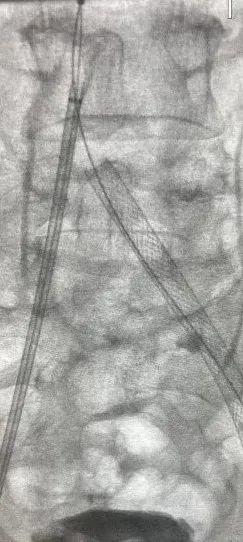

▲术中血栓保护

(支架植入过程)